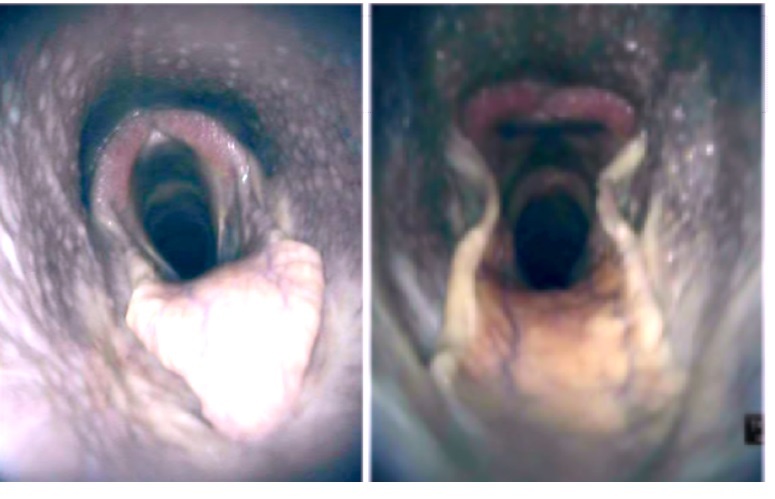

FIGURE 13 B, The corresponding right Plica vocalis at 30-50 days postsurgery on endoscopy. The Plica vocalis abscess clearly seen as a yellowish-greenish

mass covered in mucoid material (white arrow). Right to the left of the image